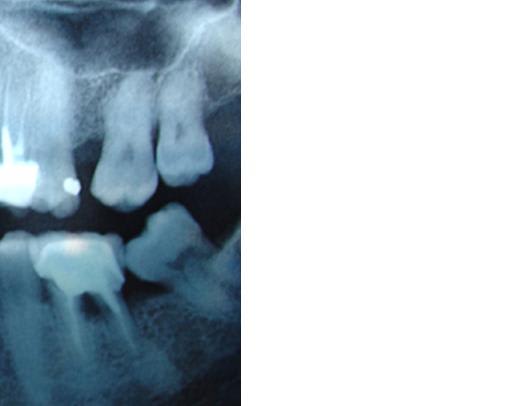

images?

de dieu, ce fut laborieux!!!!!! mais quelle idée de tout changer tout le temps sur le forum????

Ps: on peut noter le tartre encore présent sur la face mesiale de la 38 versée/mésialée.... on fera ça + tard lors de la litho/laser. Ca prouve bien que malgré tous les handicaps cumulés par ces 2 dents le seul traitement local a déjà été trés efficace.

oui on voit bien la corticalisation preuve que tout est au repos au niveau du parodonte profond ....